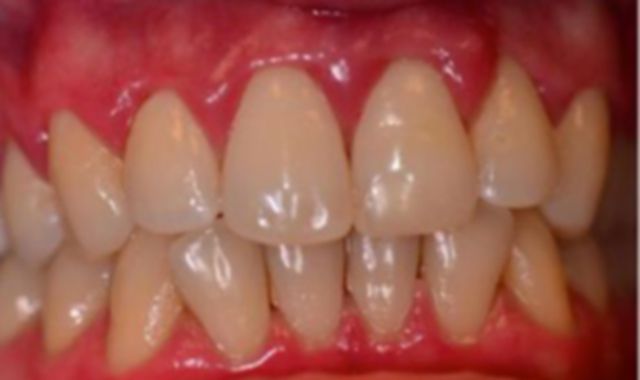

“But how could this have happened?” he asks. “I have done everything right.” The usual answers are given. He is told he has a bacterial infection and tartar buildup under his gums and that a good deep cleaning is recommended. Three months later, following the first round of root planing, there is no change to his tissues. He is treatment planned for another round of root planing, and this time his insurance will not be covering it. No blood tests are performed to identify possible systemic health issues, and nothing out of the ordinary is suspected. The patient is thought to have bacterial infection. Several months after the second round of root planing he continues to have severe inflammation and redness, with moderate generalized bleeding on probing, and apparently no change to disease activity. He is referred to a periodontist.

The periodontist examines him and quickly recommends another round of root planing. He feels good to be there and feels confident that his issues will finally be solved in the capable hands of this highly qualified professional. He will pay the out of pocket expense for full mouth root planing again. In addition he will be paying for antibiotics to be placed under his gums in an attempt to better control his “infection.” Four weeks later he is re-evaluated, there is no response at all; he still has severe inflammation and redness with moderate bleeding throughout.

The fourth round of root planing is performed and more money is spent to follow some truly puzzling and insane guidance: Do the same thing over and over and expect a different result. Several months later, there is still no response and he has now spent more than $4,000 with no change to his inflammatory disease. Eighteen months have passed since his initial diagnosis of active moderate stage periodontitis with more severe localized attachment loss becoming alarming at this point.